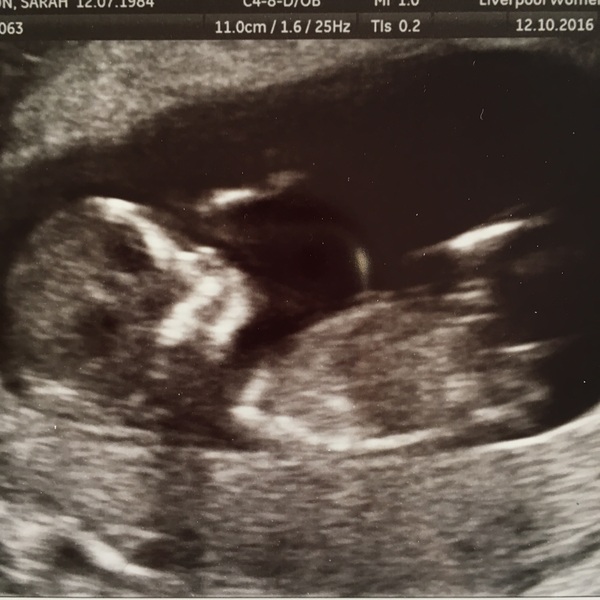

Just got back from my scan. One incredibly wriggly baby dated at 12+3 so I'm a bit ahead. Due date is now 23 April 2017.

Oh thats a LOVELY picture Sarah

Really great scan picture sarah

That's a gorgeous scan picture sarah congratulations!